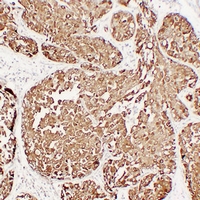

Mouse anti-MUC1 Monoclonal Antibody

PUM; Mucin-1; MUC-1; Breast carcinoma-associated antigen DF3; Cancer antigen 15-3; CA 15-3; Carcinoma-associated mucin; Episialin; H23AG; Krebs von den Lungen-6; KL-6; PEMT; Peanut-reactive urinary mucin; Polymorphic epithelial mucin; PEM; Tumor-associated epithelial membrane antigen; EMA; Tumor-associated mucin; CD227,MUC1

WB, IHC